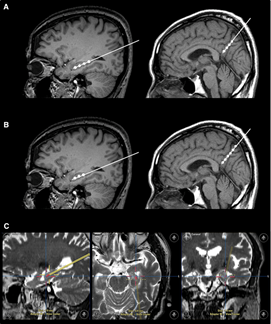

2023年1月24日,國際學(xué)術(shù)期刊Movement Disorders (運(yùn)動障礙)發(fā)表一篇研究性文章。研究者從胎兒中腦分離制備出多巴胺神經(jīng)祖細(xì)胞,移植到患者的大腦中。設(shè)計方案:給15名患者(年齡<70歲)注射了三種劑量的細(xì)胞量(4×10*6,12×10*6,40×10*6細(xì)胞),隨后進(jìn)行12個月的隨訪。研究結(jié)果顯示:低劑量組的運(yùn)動能力恢復(fù)效果為11.6%,中劑量組為26%,高劑量組為40%。此外,沒有副作用,如出血、免疫排斥、炎癥和腫瘤形成。